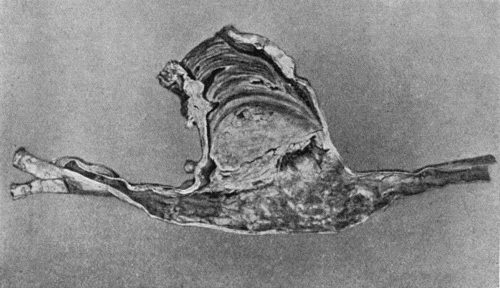

156.Caseating focus in Upper End of Fibula 513

64.Genealogical Tree of Hæmophilic Family 278